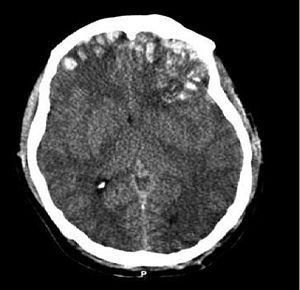

Traumatic brain injury